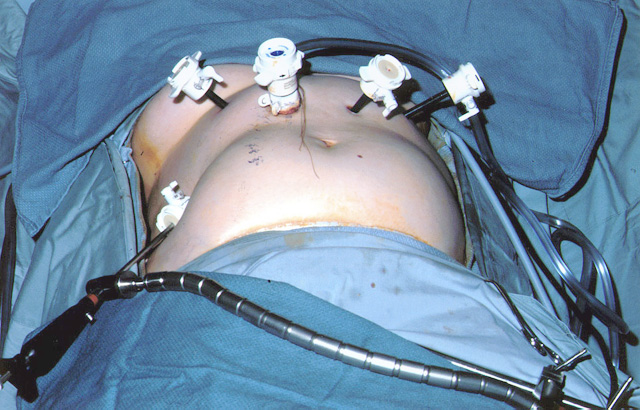

![]() |

| Figure 2: Laparoscopic port-site placement for repair of giant paraesophageal hernia. |

The patient is positioned supine on the operating table, and the surgeon works from the right side with the assistant on the left. Four 5 mm and one 10 mm laparoscopic ports (Versaport, United States Surgical Corporation (USSC); Norwalk, CT) are placed in the upper abdomen (Figure 2). The left lateral segment of the liver is retracted anteriorly with a 5 mm flexible retractor (Snowden Pencer, Genzyme; Tucker, GA) and secured to a stationary holding device (Mediflex; Islanda, NY).